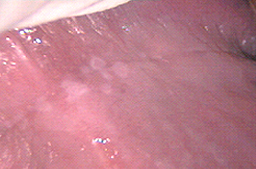

Lesiones por vph en región peri anal y ano en forma de condilomas acuminados.